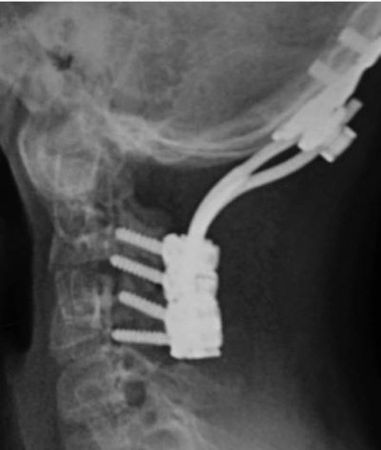

В – задняя инструментальная репозиция и фиксация системой Summit (De Puy Spine inc.) Механическая и неврологическая нестабильность устранены. Полное неврологическое восстановление.